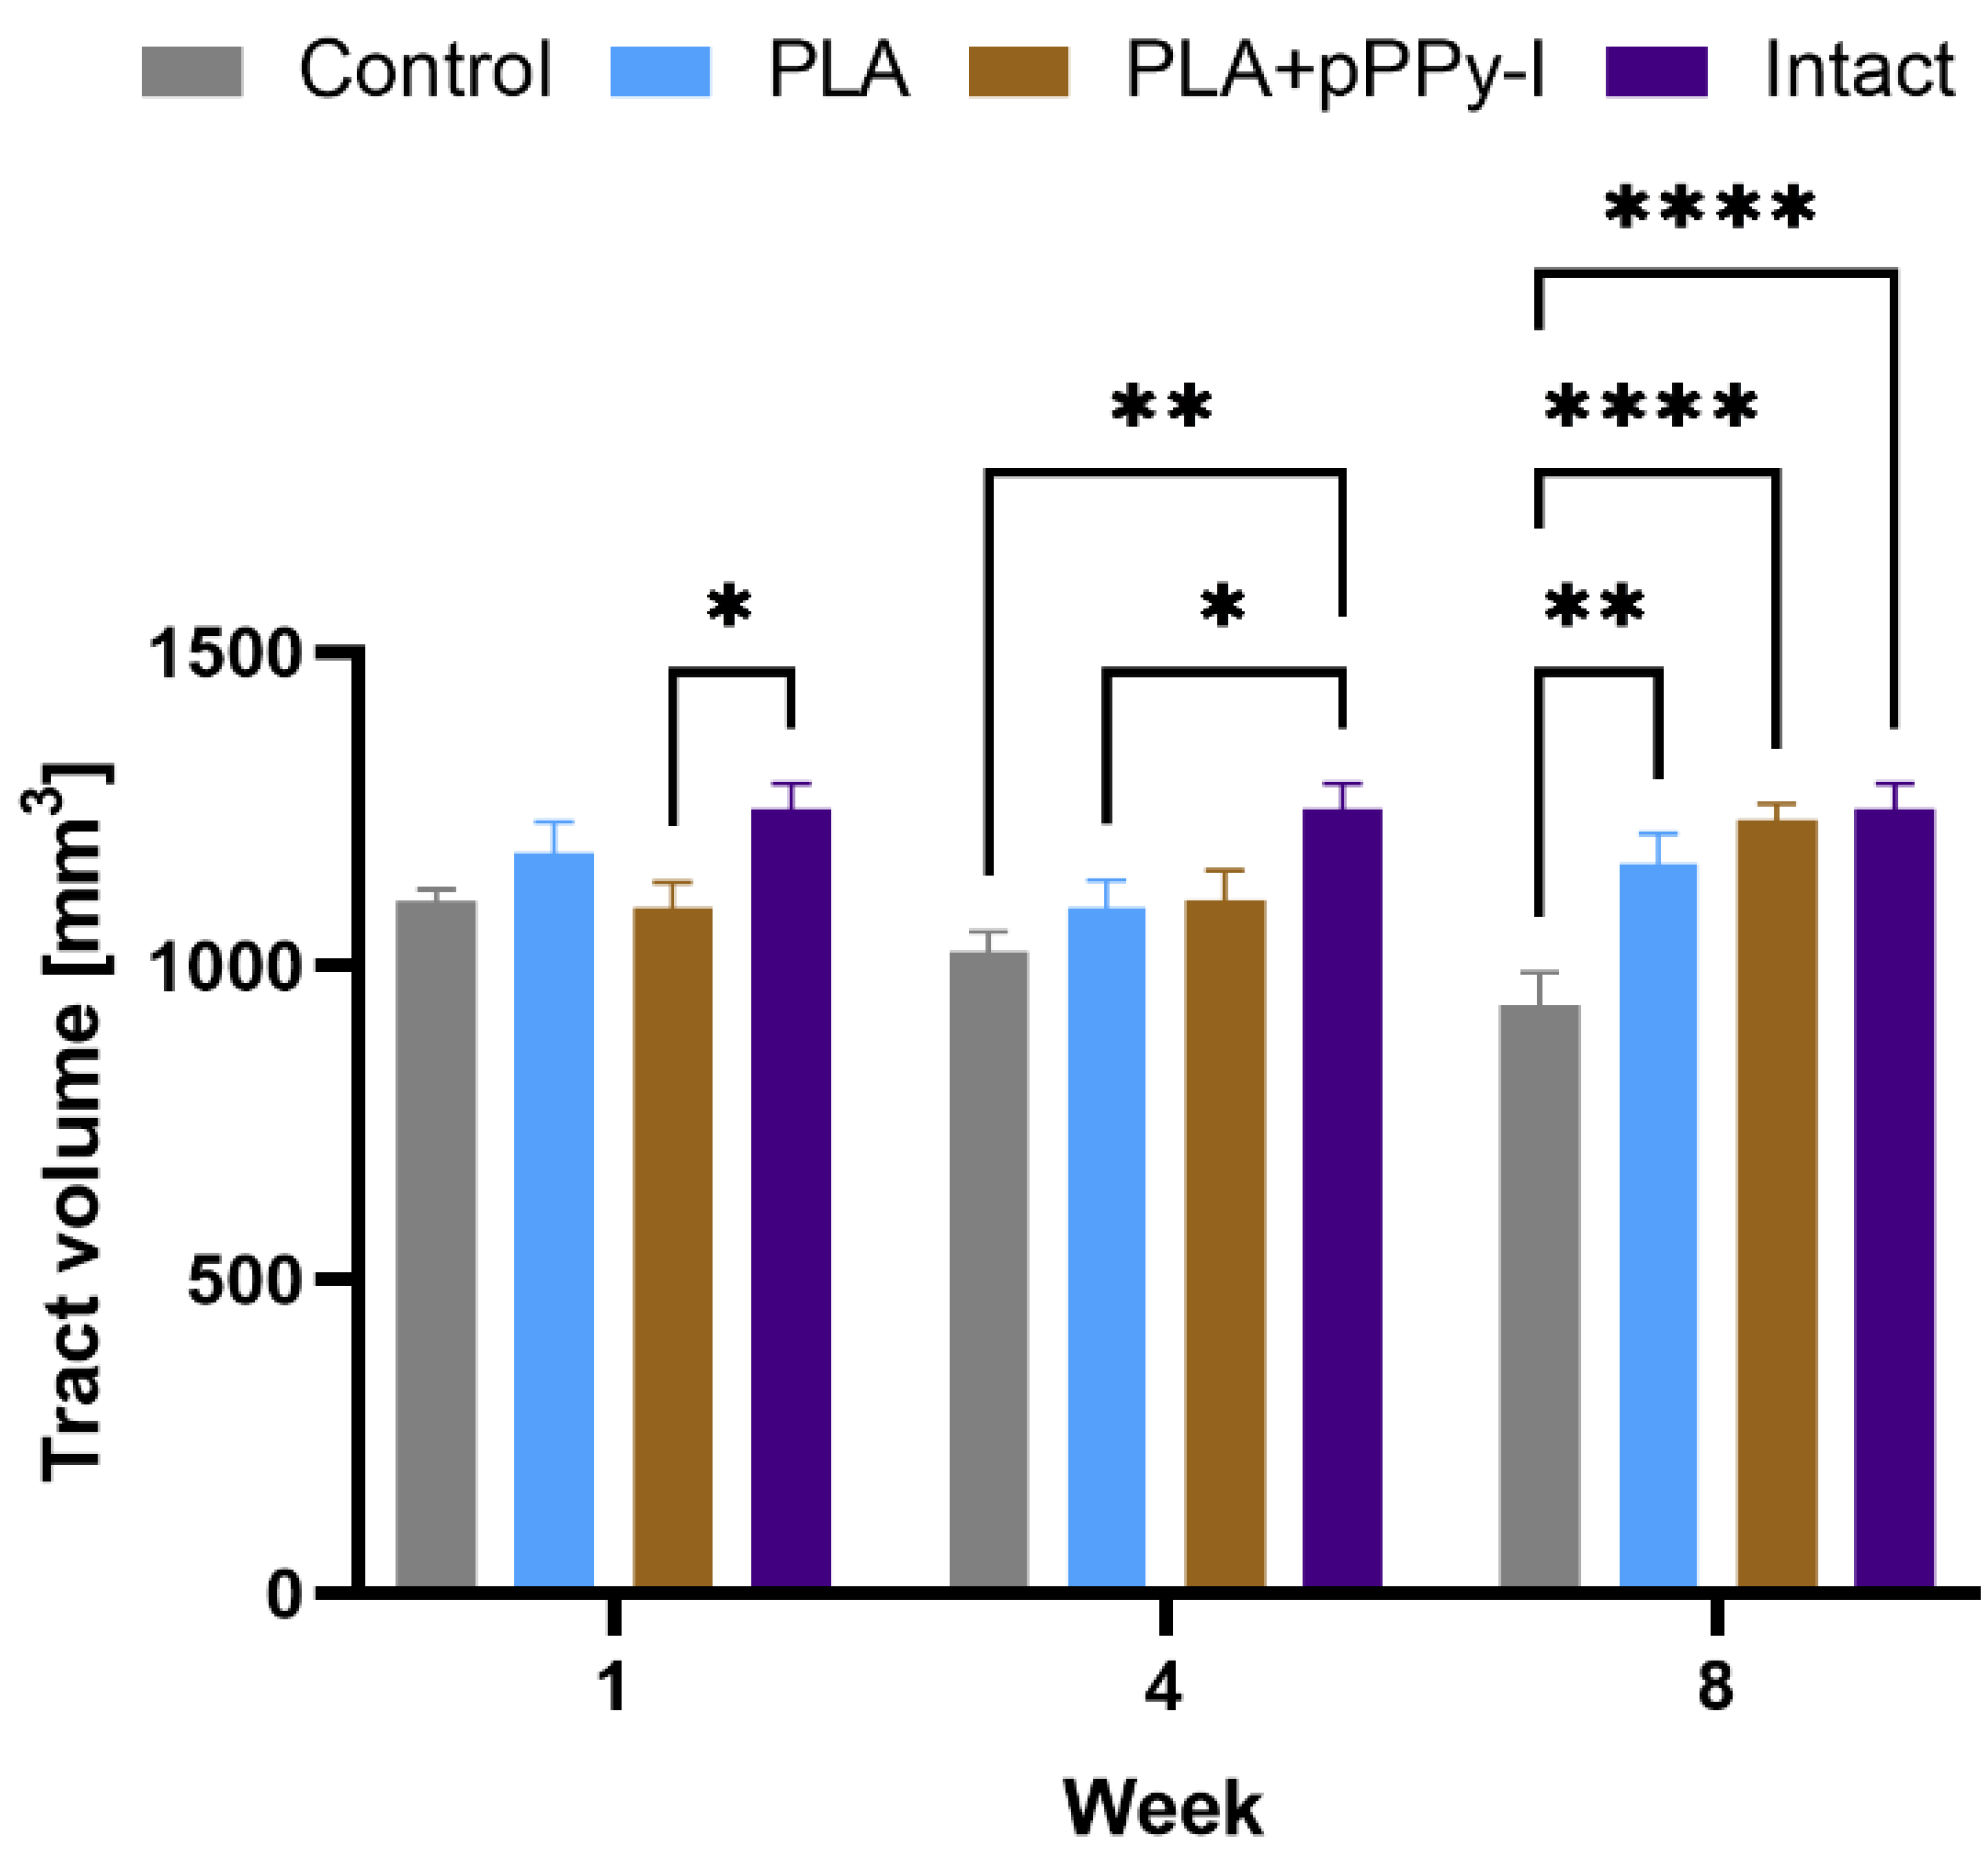

3.4. Recovery of Structural Damage by the Fibrillar Scaffolds